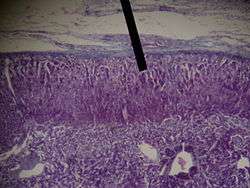

The zona glomerulosa of the adrenal gland is the most superficial layer of the adrenal cortex, lying directly beneath the renal capsule. Its cells are ovoid and arranged in clusters or arches (glomus is Latin for "ball").